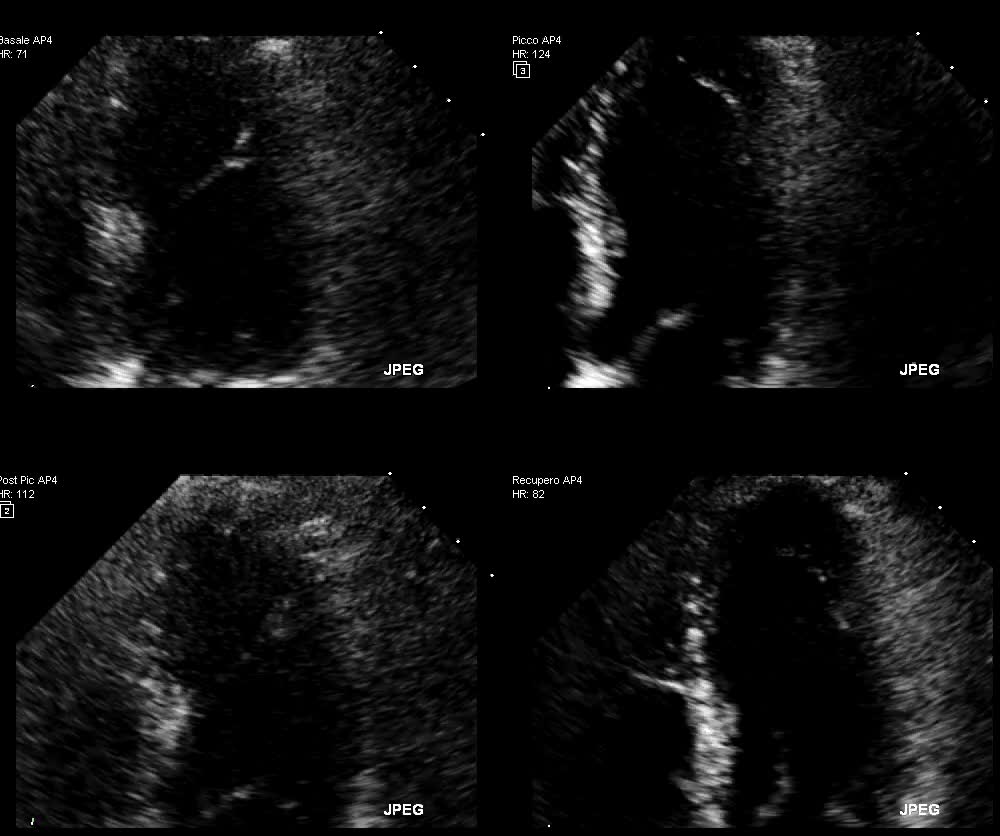

Alterazioni cinetica

Autore:

Anna Maltagliati